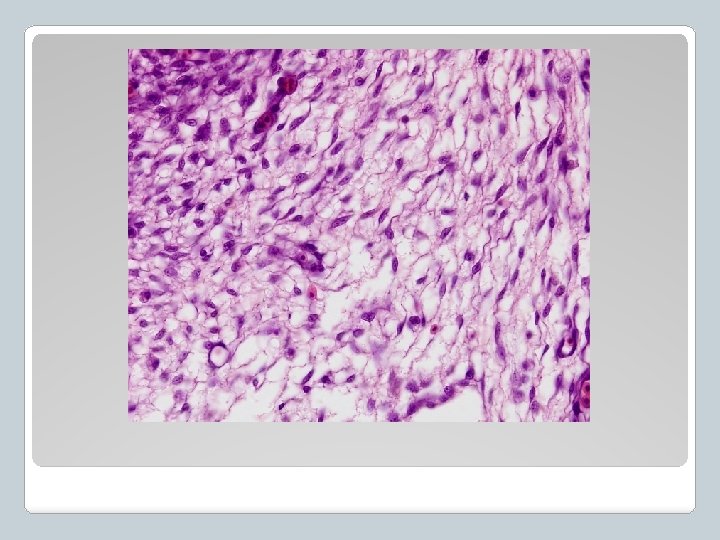

Se encuentra en la capa inferior de la piel (dermis) Muy fuerte Menos flexible que el T. conectivo laxo Funciones Sostén, transmisión de fuerzas mecánicas Ej. Forma tendones y ligamentos Composición Fibras de colágeno Tejido Conectivo Denso